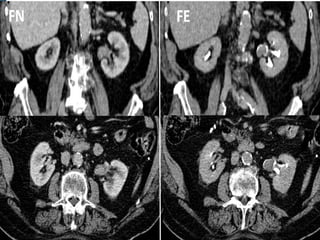

• #40 NEOPLASIA UROTELIAL PIELOCALICIAL DERECHA. La UIV muestra defecto de repleción pièlico irregular que se extiende a grupo caliacial superior.

• #41 NEOPLASIA UROTELIAL PIELOCALICIAL DERECHA. El estudio axial por TC demuestra el defecto de repleción piélico irregular que se extiende a grupo calicial superior correspondiente a la neoproliferación.

• #42 TUMOR UROTELIAL PIELOCALICIAL. Reconstrucciones coronales de TCMD en fase nefrográfica y en fase excretora que demuestran la existencia de una lesión neoproliferativa piélica derecha. La lesión presenta densidad de partes blandas y realza con contraste en FN, mostrándose como un defecto y distorsión de la repleción en FE.